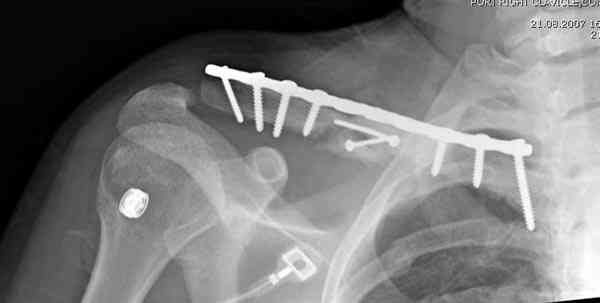

Второй случай тоже недавно оперирован по поводу

ложного сустава, в марте травма, через 4.5 половиной

операция..

Описанный случай это больная моего партнера, мы недавно случай разбирали на нашей конференции (Morbidity and Mortality Conference аналог клинического разбора)

Выставлен как пример, к чему может привести

неудачно выбранный фиксатор.